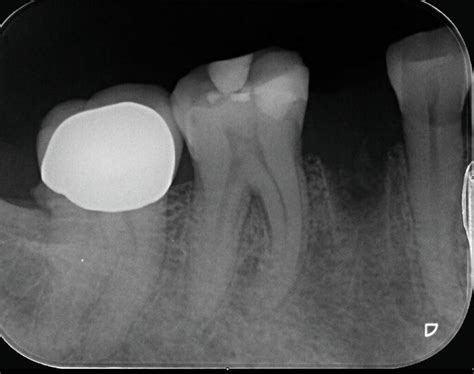

Um zu verstehen, was bei einer Zahnextraktion genau passiert, lohnt sich ein kurzer Blick darauf, wie ein Zahn im Kiefer verankert ist. Zwischen Zahn und Kieferknochen befindet sich ein schmaler Spalt, der von feinen Fasern überbrückt wird. Sie halten den Zahn an seinem Platz und sorgen dafür, dass er sich beim Kauen leicht mitbewegen kann. Je grösser die Wurzeloberfläche ist, desto mehr solcher Fasern gibt es. Deshalb lassen sich Frontzähne meist einfacher entfernen - sie haben nur eine einzige Wurzel.

Schematische Darstellung einer Zahnextraktion